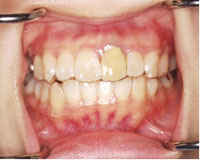

治療前

右下、糸切り歯のかみ合わせが上下逆になっている状態

患者さまご自身は、長年見た目が気になり、治したかったが、目立つ装置をつけるのが嫌でそのままにしてこられました。

しかし、時間が過ぎるにつれだんだんと下の歯が飛び出してきました。.